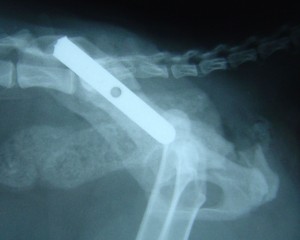

One common component in a pelvic fracture is a fracture involving the iliac wings, the flattish bones that form the walls of the pelvis. The iliac wings link the ball and socket joints on each side with the sacrum and the vertebrae at the bottom of the spinal column. As such, the iliac wings are the route by which force is transmitted from the back legs to the rest of the body. They are essential to the integrity of the weight-bearing axis of structures.

When the iliac wing fractures and causes loss of weight bearing, there can be a severe compromise to the dimensions of the pelvis. If the pelvic dimension aren’t restored, this can have big implications for the passage of faeces (and foetuses in un-neutered females) along the pelvis in future.

When the iliac wing fractures, this can lead to severe damage/pressure on the significant nerve trunk to the hind limb on that side, which causes pain and dysfunction.